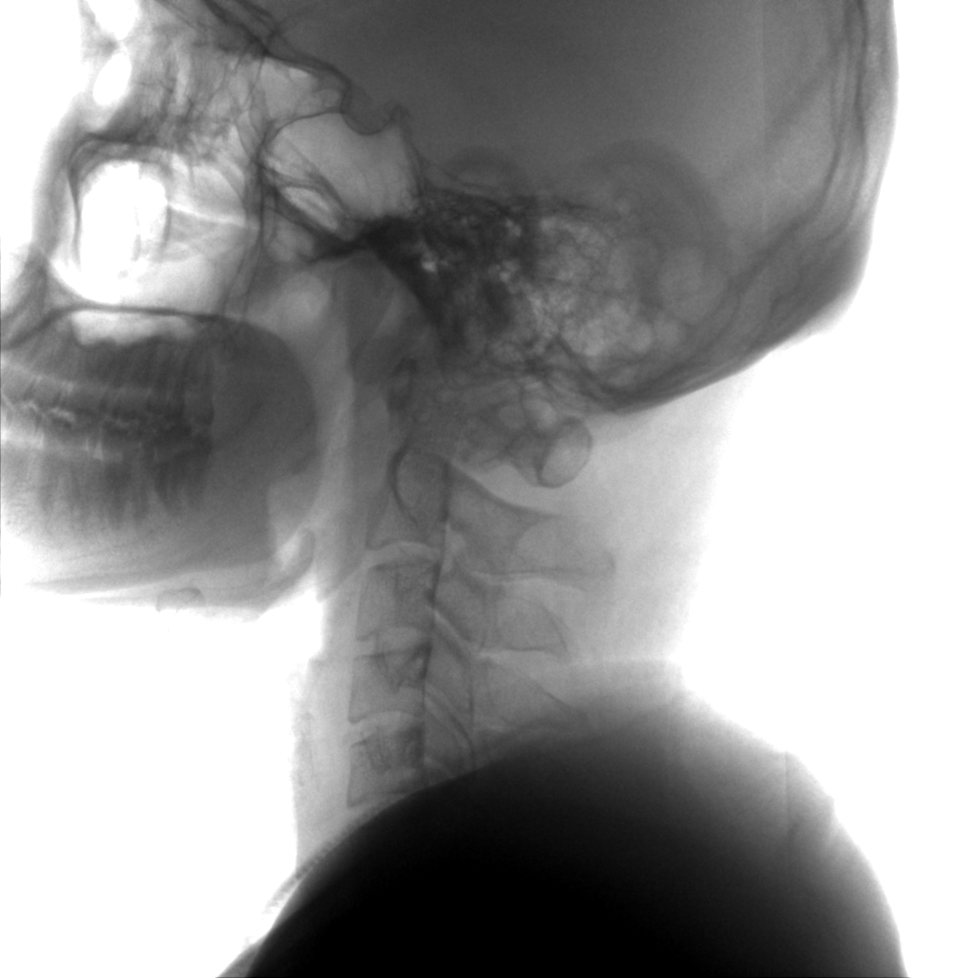

術(shù)中三維成像和橫斷面圖像提供多角度的手術(shù)診斷信息,輔助醫(yī)生進行術(shù)中評估判斷,諸如骨折復(fù)位情況和內(nèi)植入螺釘?shù)某叽绾臀恢?,輔助手術(shù)更好地完成。

提供更大的術(shù)中三維成像視野,采集更多圖像信息,可一次拍全全段頸椎、全段腰椎、七節(jié)胸椎、雙側(cè)骶髂關(guān)節(jié)、股骨頭及單側(cè)盆骨。